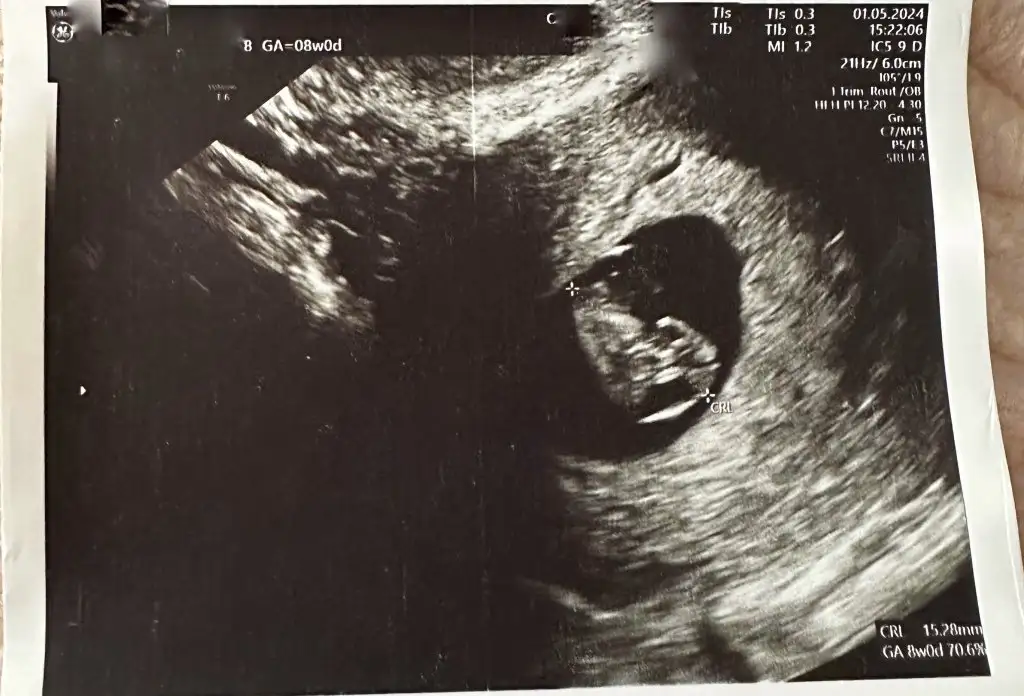

01 Mayıs ta ultrason bu şekildeydi inşallah hala oralarda bi yerdedir🙏🏻